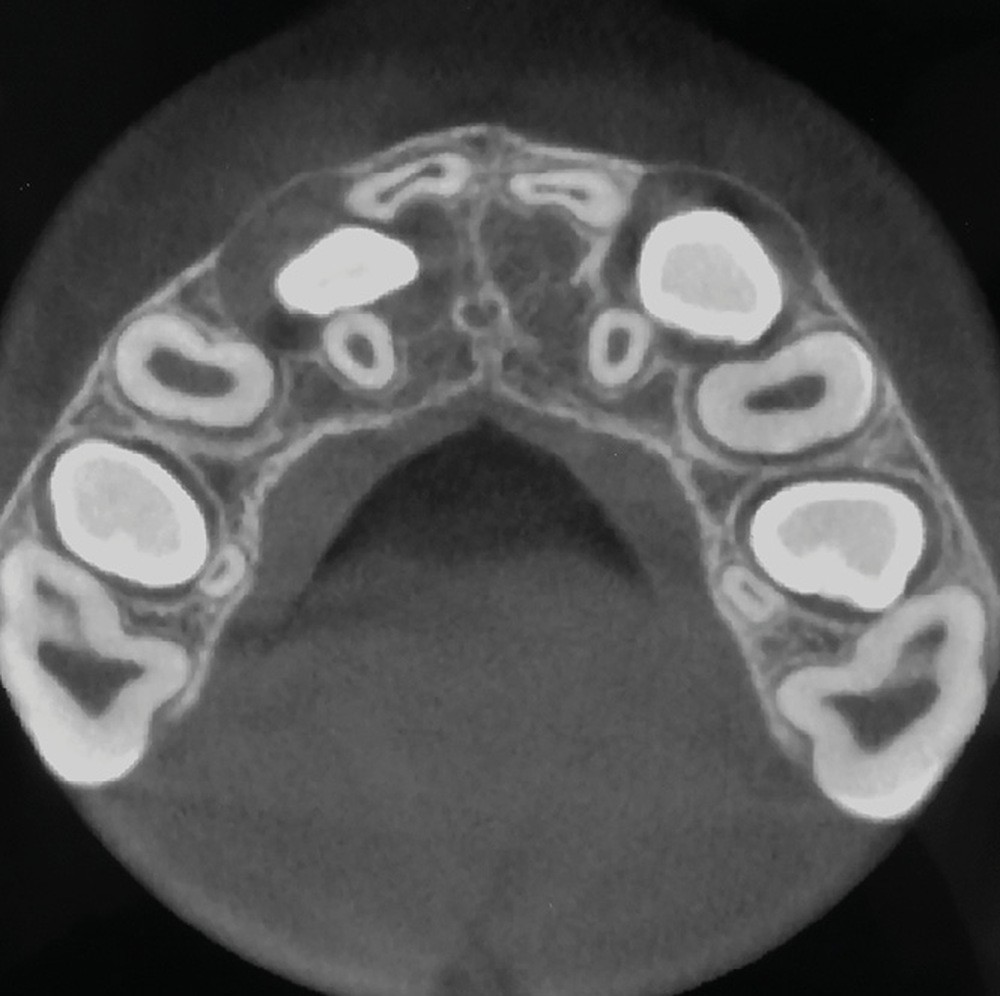

Le profil est convexe et associé à une inocclusion labiale au repos. Il s’agit d’une classe II squelettique sur un schéma facial normodivergent. Les rapports occlusaux sont de classe II bilatérale (complète au niveau molaire) avec des incisives inférieures vestibulo-versées. La 21 est géminée et la 11 vraisemblablement fusionnée avec un germe surnuméraire, sans altération de la formule dentaire. Du fait du diamètre mésiodistal fortement augmenté des incisives centrales, et du manque de place à l’arcade maxillaire qui en découle, les 12 et 22 sont en inversé d’occlusion en palato position. Les 53 et 63 sont persistantes sur l’arcade avec une inclusion en transposition incomplète de la 13, dont la cuspide se situe entre la racine de la 12 et celle de la 11 résorbée (fig. 1d-g).